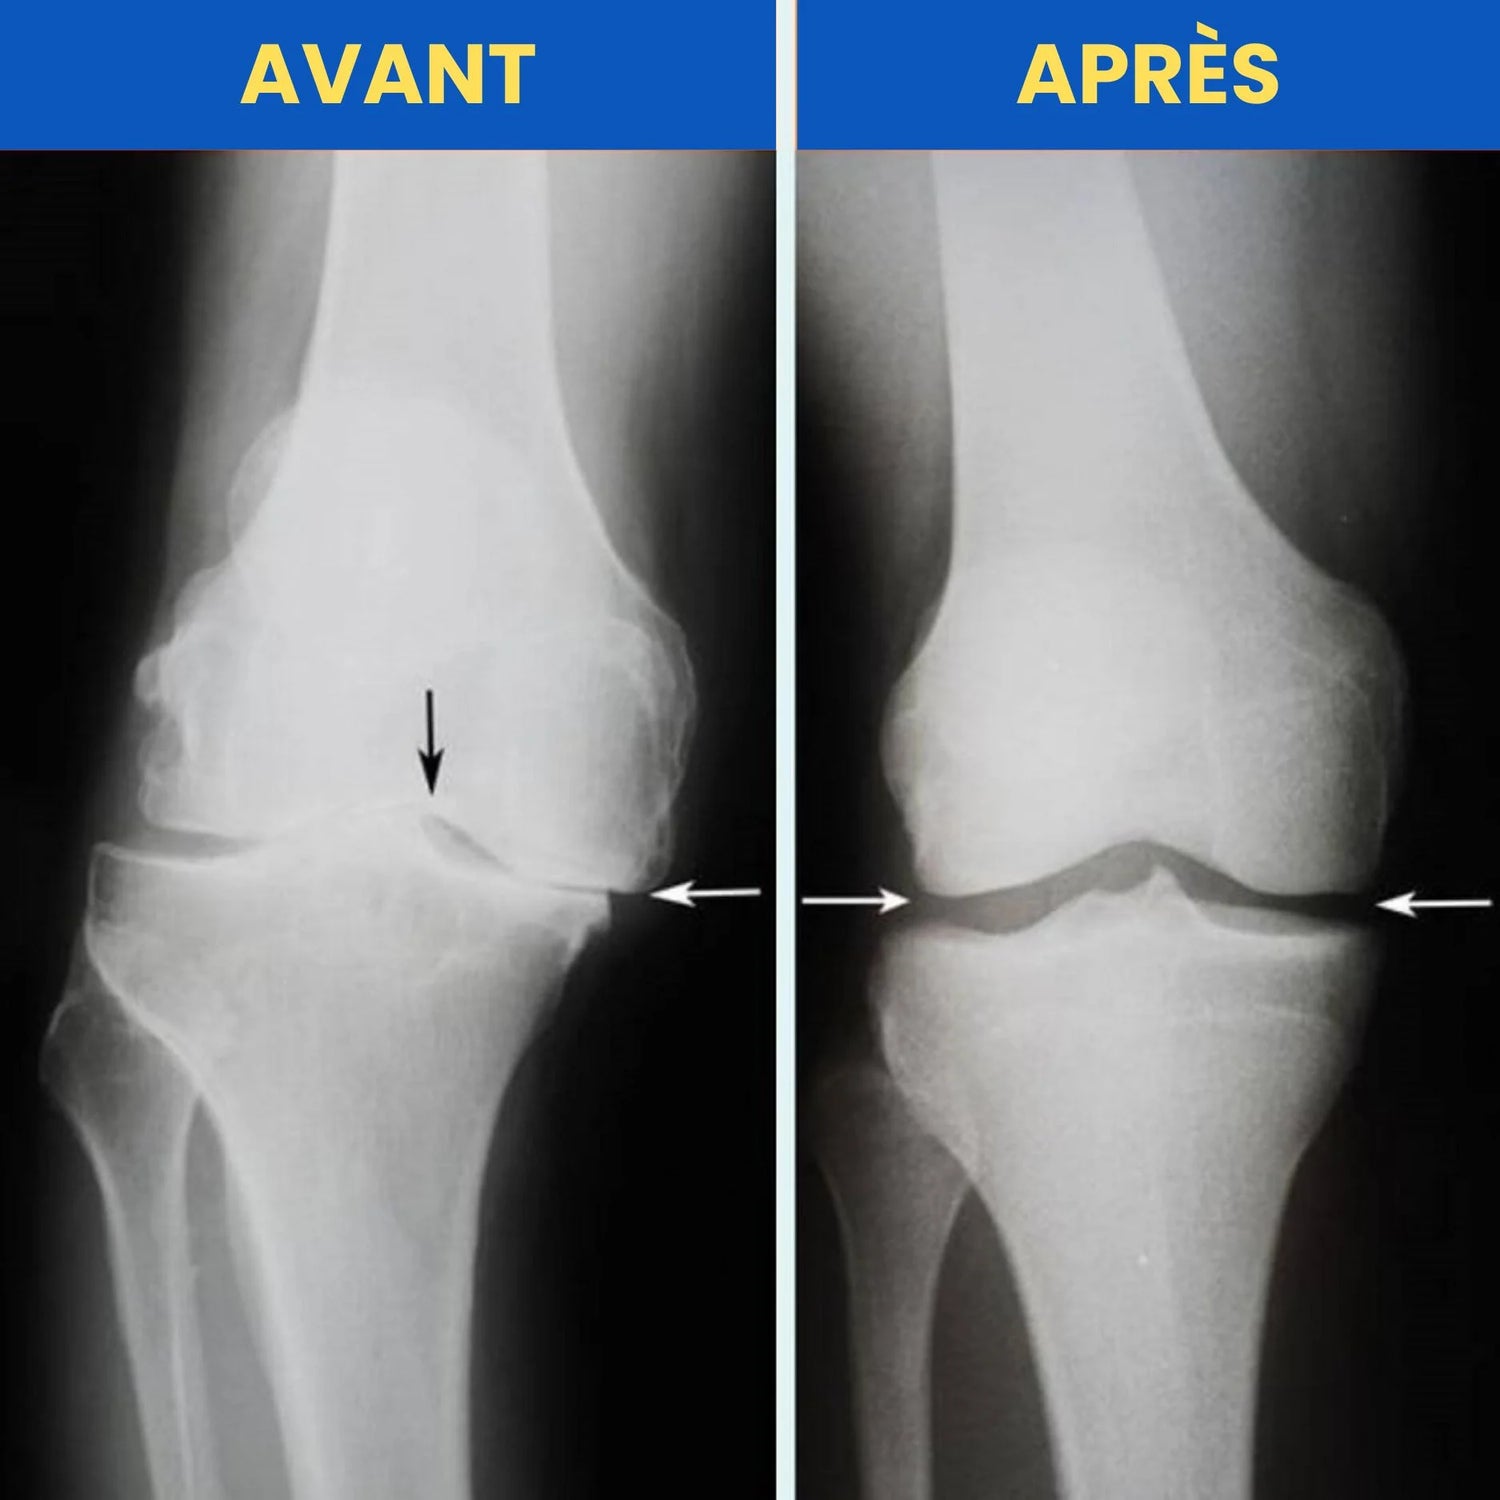

Lorsque vous ressentez une douleur persistante au genou, le véritable problème vient d’un mauvais alignement de l’articulation et de l’usure progressive du cartilage.

Un genou bien aligné répartit uniformément le poids du corps et absorbe les chocs sans irritation.

Mais avec l’âge, les blessures ou un mode de vie sédentaire, cet alignement naturel est perturbé.

Une mauvaise répartition de la pression sur l’articulation

Une usure accélérée du cartilage

Les douleurs qui s’intensifient à chaque mouvement

C’est ainsi que l’arthrose et les douleurs chroniques s’installent, limitant progressivement votre mobilité et votre qualité de vie.

Lorsque le genou est mal aligné, chaque mouvement peut aggraver les douleurs.

Grâce à la Technologie d’Alignement Biomécanique, FlexiGenoux™ réaligne naturellement la rotule, réduit la pression sur le cartilage et soulage la douleur à la source.

Résultat : plus de stabilité, moins de tension, une marche fluide et un genou qui retrouve sa fonction naturelle.